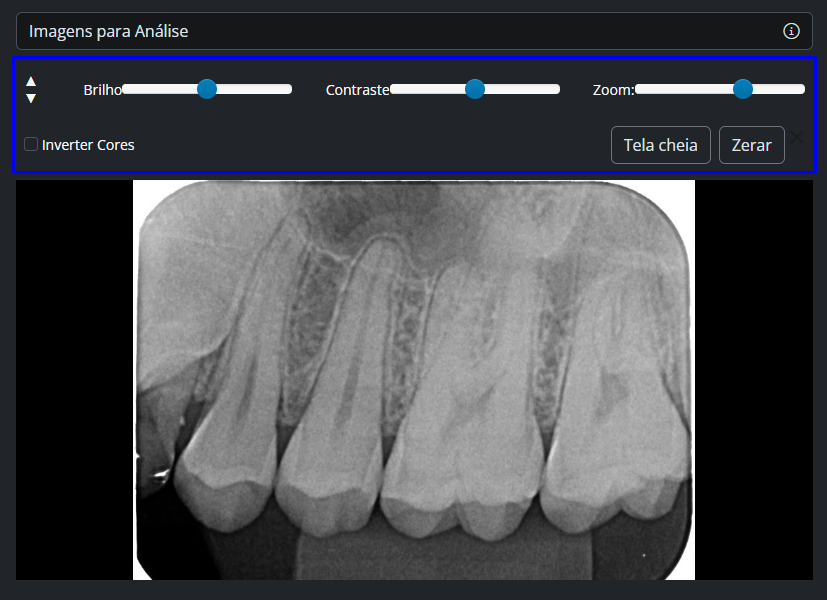

Imagens para Análise

Na galeria, você pode:

- clicar sobre qualquer imagem para abrir o visualizador

- utilizar as ferramentas de análise

⚠️Dica:

Se utilizar duas telas, é possível manter:

- uma aba com o visualizador

- outra com o editor de texto